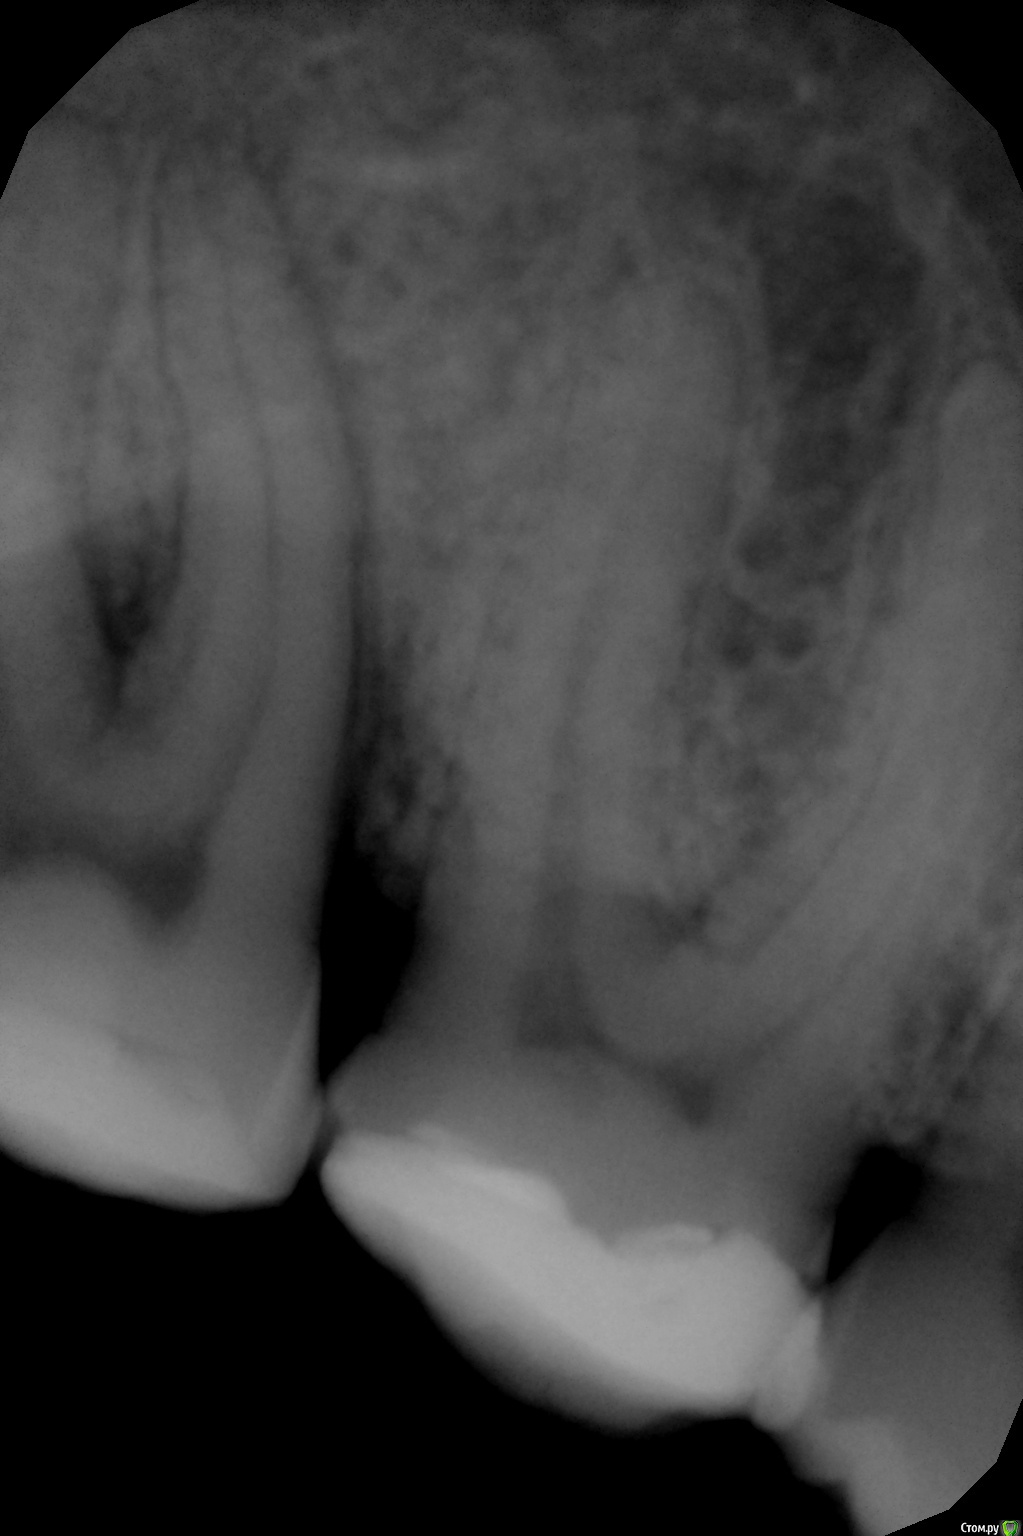

Yulechka1986 Опубликовано 12 сентября, 2016 Поделиться Опубликовано 12 сентября, 2016 Уважаемые коллеги! Прошу совета! Практически интактная семерка, 3.7. обратился пациент по поводу скола пломбы, боли при накусывании. После лечения боли продолжаются, на снимке обнаружена гранулирующее изменение костной ткани. Депульпировать? Как лечить гранулему? Выводить туда кальций? Ссылка на комментарий

Yulechka1986 Опубликовано 12 сентября, 2016 Автор Поделиться Опубликовано 12 сентября, 2016 Почти интактный? Ну это Вы погорячились. Я никаких гранулем на апексах не вижу. Неплохо бы снимок перевернуть.Тест на витальность делали?Мне карман дистально не нравитсядумаете пломба близко к рогу пульпы? Карман есть, между корней разряжение костной ткани.. Ссылка на комментарий

vse32 Опубликовано 12 сентября, 2016 Поделиться Опубликовано 12 сентября, 2016 Похоже начинаю понимать. 37 это тот, что обрезанный? Мне кажется там паро проблемы есть. И не без участия плохого контакта 36-37.Тест на витальность нужен. Ссылка на комментарий

Бардо Опубликовано 12 сентября, 2016 Поделиться Опубликовано 12 сентября, 2016 (изменено) Видимо справа. Депульпировать не надо. Делайте адекватные реставрации на 6 и 7, устраняйте проблему с пародонтом Изменено 12 сентября, 2016 пользователем Бардо 2 Ссылка на комментарий